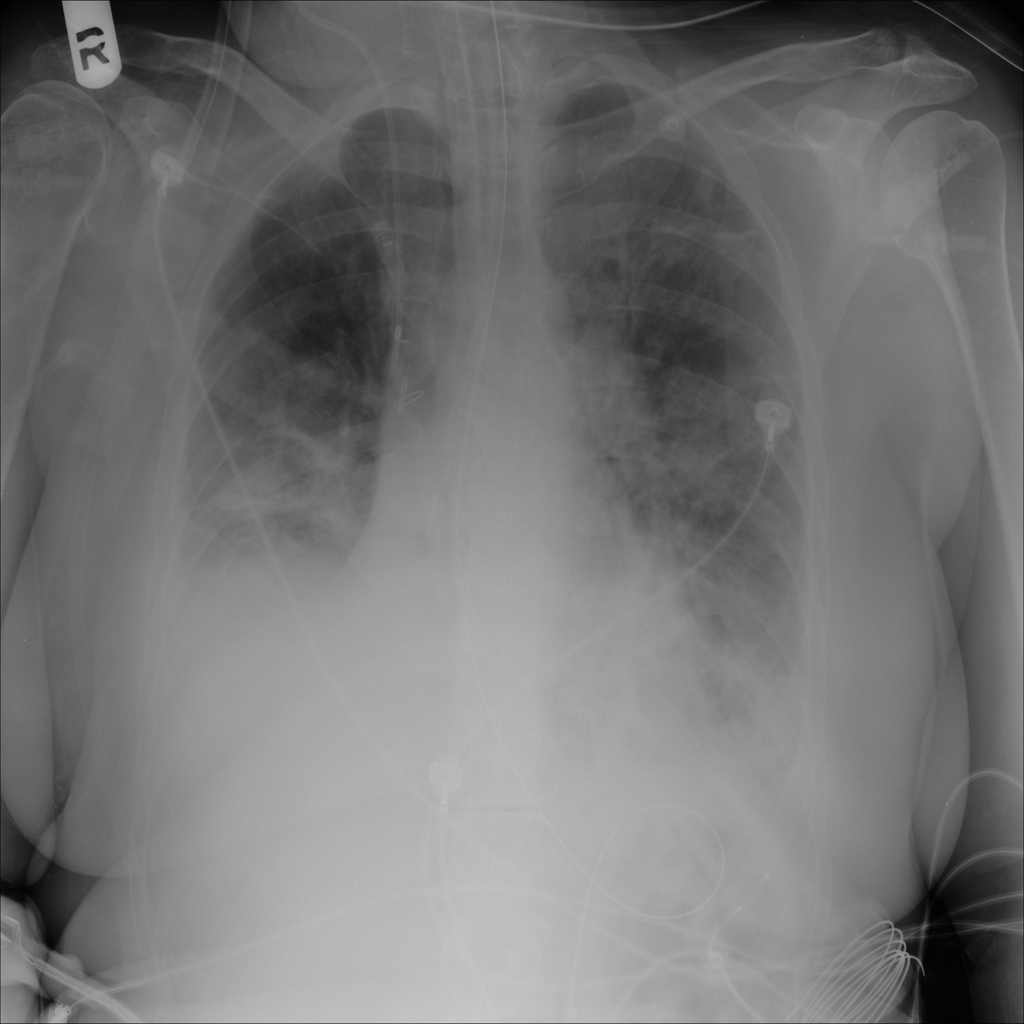

PAT-86C8 · IMG-000Effusion

PAT-86C8 · IMG-000

PA